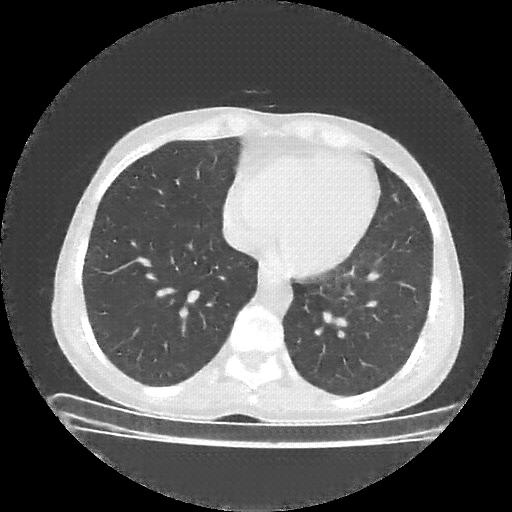

Image Grid

4×3 grid: Rows show different image types (Original NATIVE, Reconstructed NATIVE, Original VENOUS, Generated VENOUS), Columns show windowing techniques (No Window, Lung Window, Mediastinum Window)

Original NATIVE CT scan (input)

No window - Raw intensity values

Original NATIVE CT scan (input)

Lung window (WL -600, WW 1500 → Low −1350, High +150)

Original NATIVE CT scan (input)

Mediastinum window (WL 40, WW 400 → Low −160, High +240)

Windowing Parameters

- No Window: Raw intensity values without windowing

- Lung Window: WL -600, WW 1500 → Low −1350, High +150 (optimal for pulmonary structures)

- Mediastinum Window: WL 40, WW 400 → Low −160, High +240 (optimal for soft tissues)